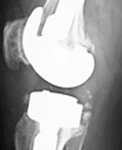

Resim 2. Revizyon ameliyatı öncesi lateral direkt grafi.

Resim 4. Revizyon ameliyatı sonrası lateral direkt grafi.